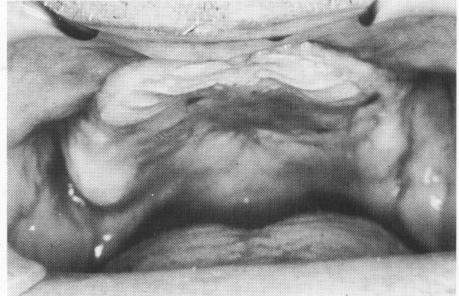

Fig. 12-109. The flattened maxillary ridge.

1 Flattened maxillary ridge